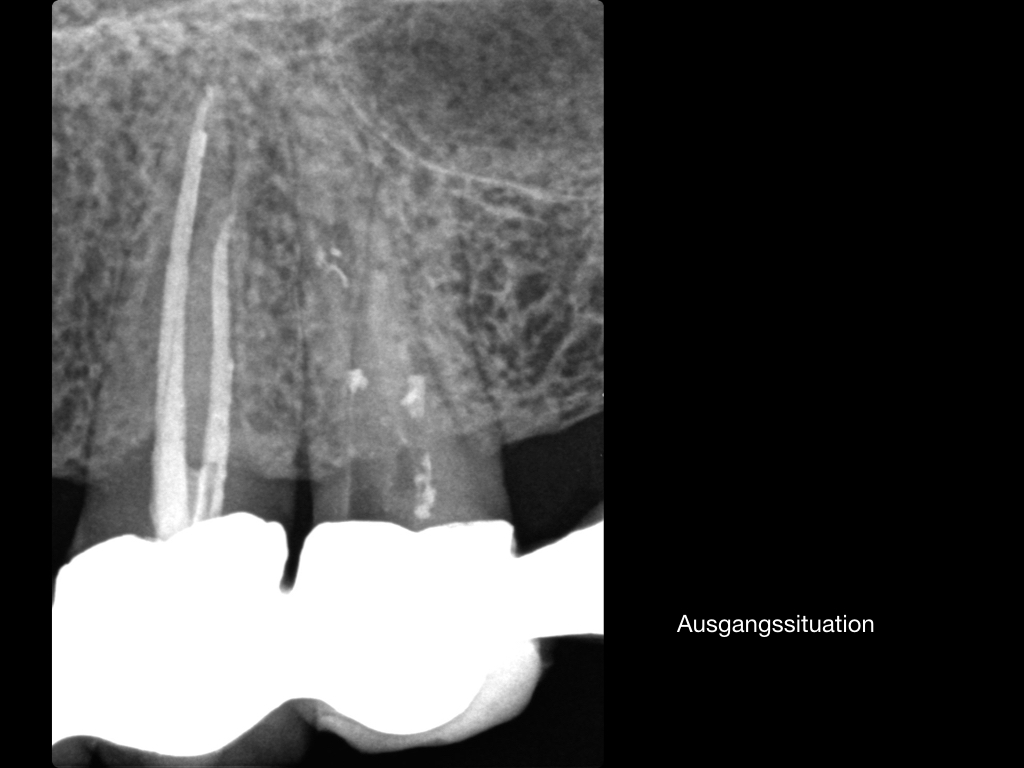

Es ist zu sehen … (2)